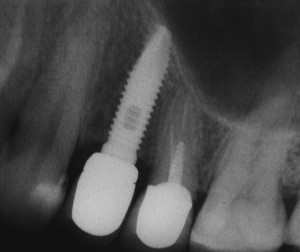

Закрытый синуслифтинг относительно малотравматичен и позволяет поднять дно гайморовой пазухи в пределах 1-4 мм, не прибегая к расширению операционной раны (рис 9, 10, 11):

Рисунки 9, 10, 11. Рентгенограммы области имплантации: слева – до операции, в центре – сразу после операции имплантации в сочетании с закрытым синуслифтингом, справа – через 12 месяцев после протезирования.